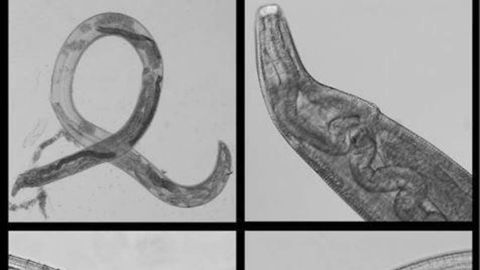

Eran tantos los insectos que la mujer recuerda tener que aplastar moscas de su cara y escupir otras tantas por la boca. Fue precisamente esto último lo que hizo que se contagiara de un parásito que habita en los insectos: la Thleazia gulosa.

Pero los hechos no se quedaron ahí. Apenas un mes después del incidente, la mujer empezó a notar irritacióin en su ojo derecho. Decidió lavárselo con agua, momento en que descubrió que tenía dentro un gusano semitransparente de una pulgada de largo. La mujer quiso inspeccionar más a conciencia su ojo y encontró un segundo gusano, así que al día siguiente no dudó en acercarse a un oftalmólogo, quien encontró y retiró un tercero.

Las muestras fueron enviadas al Centro de Control y Prevención de Enfermedades, donde identificaron que, efectivamente, se trataba del parásito antes comentado.

Los médicos le diagnosticaron, mientras tanto, conjuntivitis, para lo cual le recetaron un tratamiento con antibióticos. Pero la mujer seguía sin mejorar, por lo que consultó a otro doctor diferente. Tenía un cuarto gusano en el ojo. Retirado este último, todos sus síntomas remitieron.